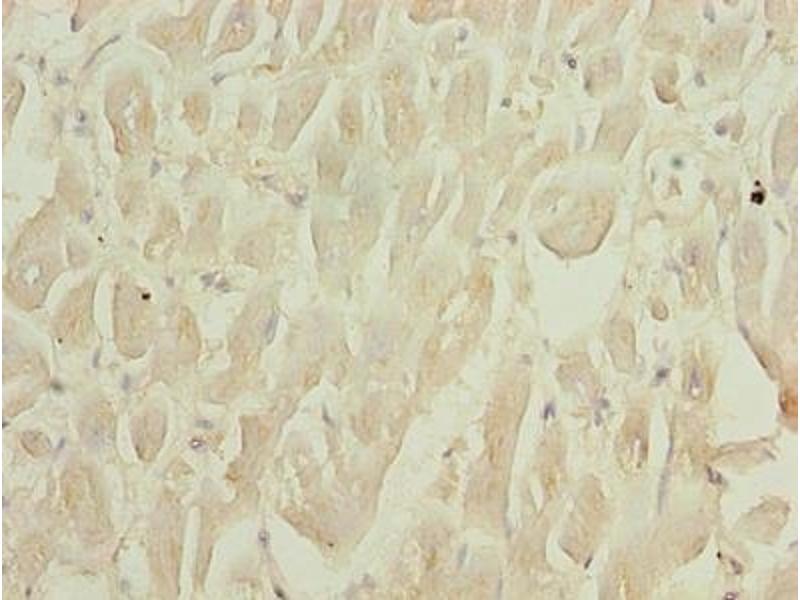

Der Kaninchen Polyklonal anti-Selenoprotein W Antikörper wird verwendet zum Nachweis von Selenoprotein W in Proben von Human. Er wurde validiert für ELISA und IHC.

ELISA, Immunohistochemistry (IHC)